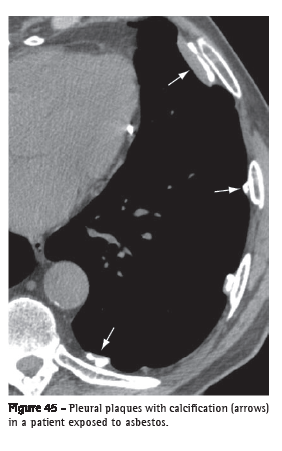

Pleural plaque (placa pleural)

Pleural plaque is focal pleural thickening, occasionally presenting calcification, of variable thickness and up to 5 cm in extension (Figure 45).(68) It usually occurs in the subcostal ­parietal pleural surface or diaphragm pleura. When the plaques are multiple and bilateral, they are almost always caused by exposure to asbestos.(69,70)